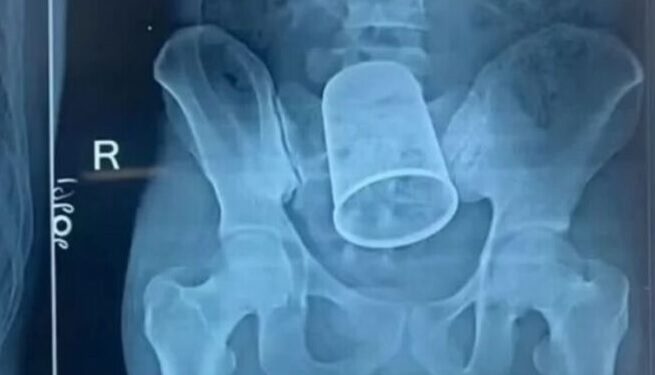

Um homem de 22 anos passou por uma cirurgia de emergência após enfiar um copo de 14 centímetros de comprimento e 7 de diâmetro no ânus durante uma noitada de cachaça~.

De acordo com os médicos do Patna Medical College Hospital, da cidade de Bettiah, na Índia, o caso deixou todos sem acreditar, até que o exame mostrou o copo.

Ele chegou ao pronto-socorro às 4 horas da madrugada com dores e sangramento no reto. Foram necessários 11 médicos para retirar o copo.